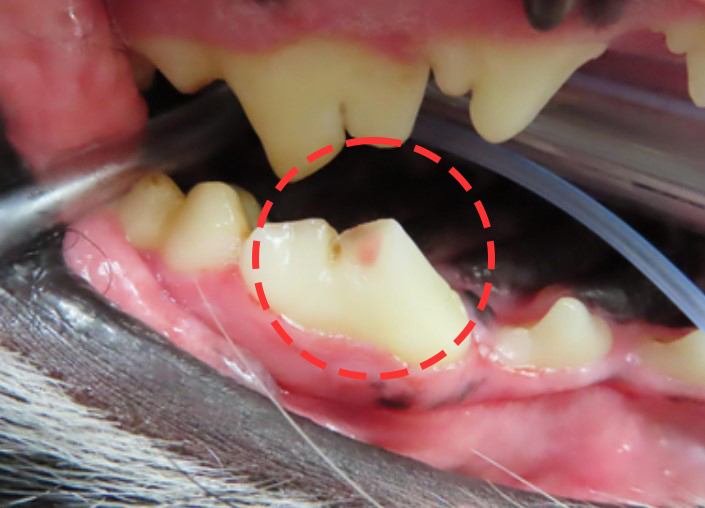

사진의 분홍색으로 보이는 부분이 신경이 노출된

골절 부위입니다.

치료 적용이 가능한 상태인지를 정확하게 확인하기

위해 치과 엑스레이 촬영 후 스케일링을 진행했습니다.